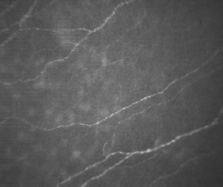

When viewed with electron microscopy, Bowman's layer appears as a felt-like composite of randomly oriented, striated collagen fibrils dispersed throughout an amorphous matrix (Fig. 12). In an adult, this layer is approximately 8 to 12 μm thick, being slightly thicker in the corneal periphery.21 Bowman's layer is acellular, except for nerve axons coursing toward the epithelium.46 Historically, electron microscopy has suggested a lack of keratocyte (fibroblast) cells within Bowman's layer, which called into question its ability to regenerate after injury or that keratocytes could migrate into Bowman's layer. In confocal microscopy views of the living eye, numerous keratocytes are observed at the level of Bowman's layer (Fig. 13).

Fig. 13. Confocal microscopic transverse image of the human Bowman's layer in vivo. Nerve axons course freely through the structure and keratocyte nuclei appear numerous and more refractile than deeper in the stroma. (500×). (Courtesy of Nidek Technologies.)